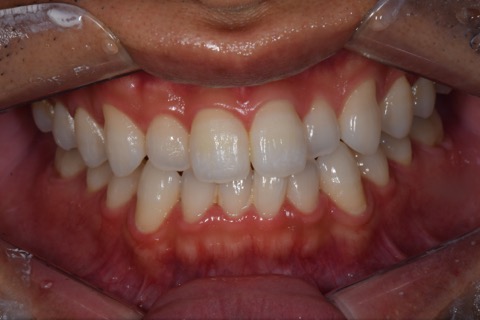

症例写真(治療後)

治療後:

矯正治療と虫歯の治療すべて終わったときの写真になります。見た目も最初の頃とは全く違いますし、お口の中もすごく綺麗です。